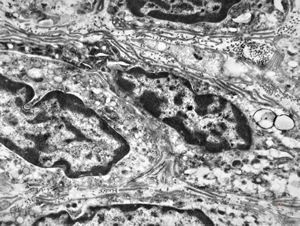

F,41y. | synovial metaplasia - capsule of implantate

F,41y. | synovial metaplasia - capsule of implantate

F,41y. | synovial metaplasia - capsule of implantate

F,41y. | synovial metaplasia - capsule of implantate

F,41y. | synovial metaplasia - capsule of implantate

F,41y. | synovial metaplasia - capsule of implantate

F,41y. | synovial metaplasia - capsule of implantate

F,41y. | synovial metaplasia - capsule of implantate

F,41y. | synovial metaplasia - capsule of implantate